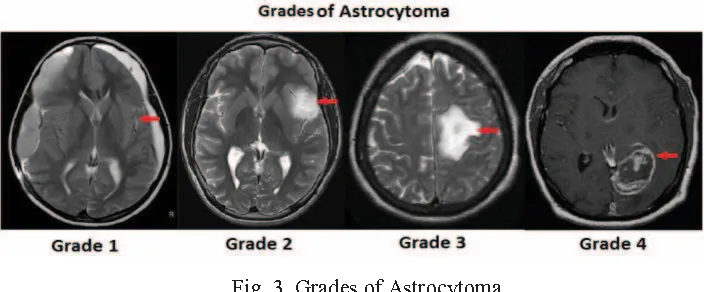

使用 BCIs 监测脑癌的方法或使用时间可能因脑肿瘤的类型而异。最常见的原发性脑肿瘤是胶质瘤,包括星形细胞瘤和少突胶质瘤。每种类型都有自己特定的分期系统。以下是最常见类型的分期:

星形细胞瘤(Astrocytomas)

I级(Pilocytic Astrocytoma):这些肿瘤生长缓慢,被认为是良性的。它们通常定义明确,通常可以通过手术切除。

II级(Diffuse Astrocytoma):这些肿瘤被认为是低级别的,浸润性较强。它们往往生长缓慢,并可能作为高级别肿瘤复发。

III级(Anaplastic Astrocytoma):这类肿瘤被认为是高级别肿瘤。它们生长速度较快,更有可能向附近组织扩散。

IV级(Glioblastoma):胶质母细胞瘤是星形细胞瘤中最具侵袭性的一种,被认为是恶性程度最高的脑癌。它们生长迅速,浸润性强,可在脑组织内迅速扩散。

星形细胞瘤的分级